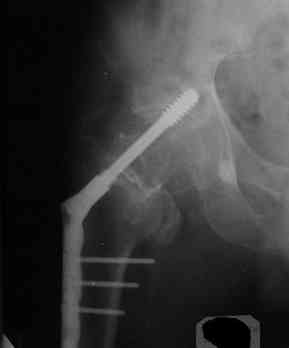

Все-таки хочу поделиться раз затронулась тема, может кому-нибудь и сгодиться. Это пример из области скорее трудноудаляемой. Пациент 50 лет, травма (низкоэнергетическая) 1,5 года назад. Оперирован через неделю (винт отечественный). Через 4 месяца выполнен контрольный снимок, сразу же возник вопрос: почему винт не телескопировался? Вопрос в общем-то так и остался без ответа.

При удалении (наркоз) после неимоверных усилий пришлось выкрутить фиксатор единым блоком и только тут все встало на свои места. См. фото.

Грустно+ Вот какие сюрпризы преподносят иногда коллеги.